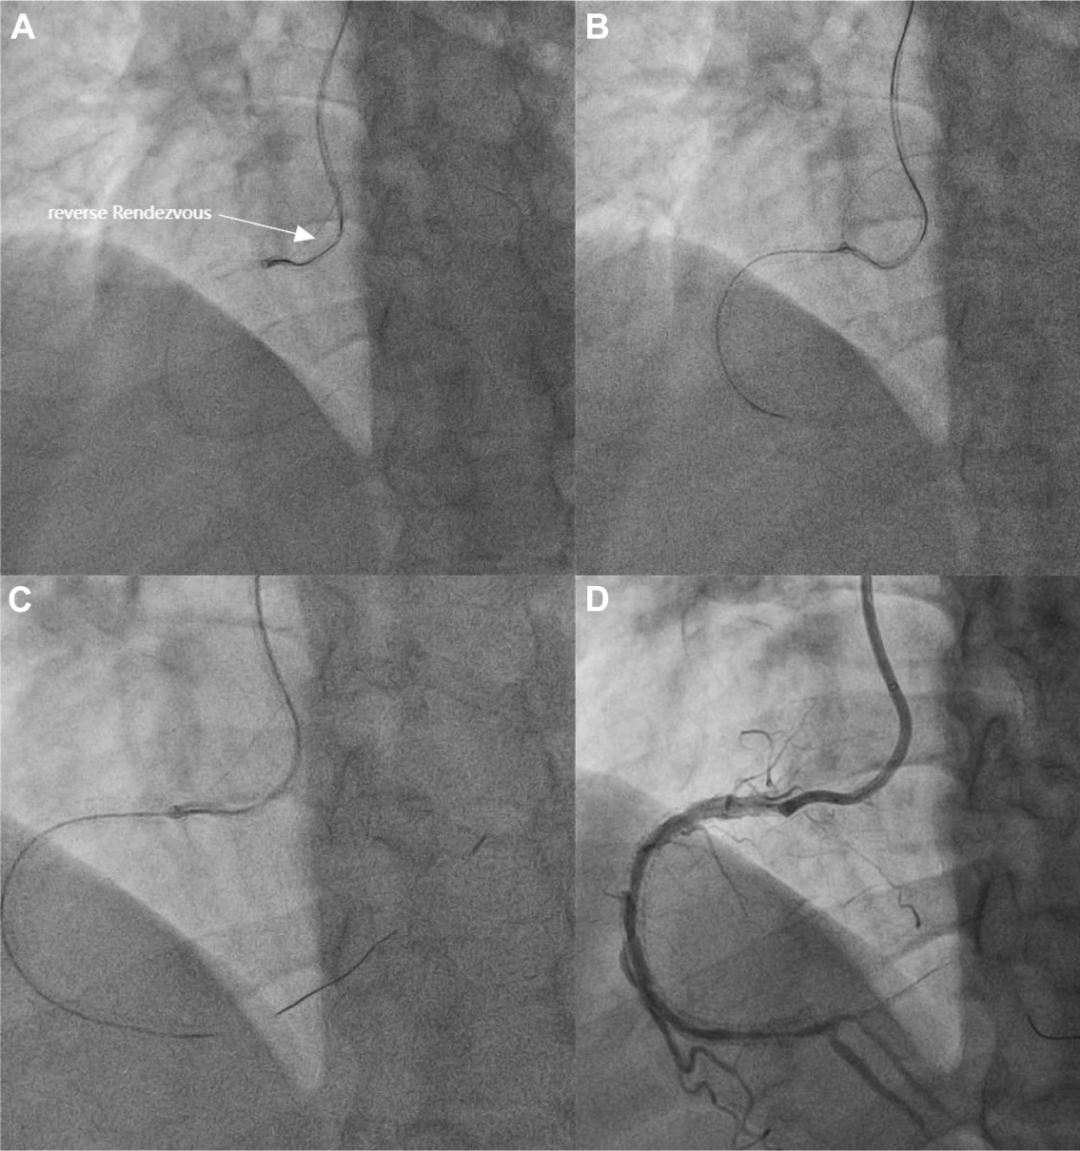

采用反向rendezvous(会师)技术,正向微导管被引导至RCA远端(图4A、4B,视频3)。

图4 正向导丝成功送达RCA远端

(A)AL 0.75指引导管中的反向rendezvous技术。(B)正向微导管通过逆向导丝送达RCA远端。(C和D)正向工作导丝成功送达RCA远端。

撤除逆向系统(导丝和微导管),将正向导丝交换为工作导丝,该导丝被成功送至RCA远端真腔内(图4C、4D,视频3)。

第四步:完成血运重建

预扩张后,在远端RCA成功植入一枚药物支架,同时采用药物球囊对中段病变进行充分扩张。

最终造影显示,支架贴壁良好,远端RCA达到TIMI3级血流(图5A、5B);左冠脉造影未发现侧支循环通道损伤(图5C)。

图5 最终结果

(A和B)RCA远端的支架最佳贴壁和TIMI 3级血流。(C)左冠脉造影未发现侧支通道损伤。